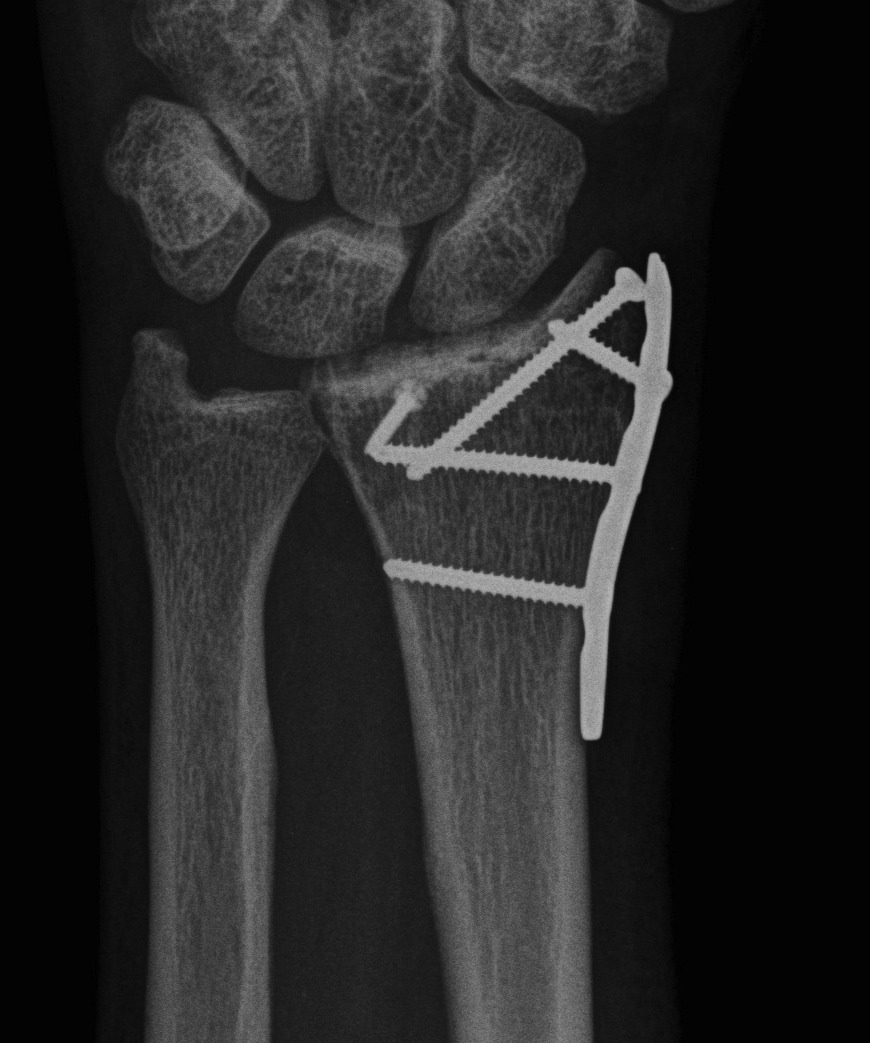

Dorsal radiocarpal dislocation with dorsal rim fracture

Dorsal radiocarpal dislocation with radial styloid fracture